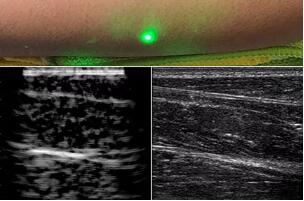

目前,研究人員已經(jīng)與健康的志愿者測試了他們的系統(tǒng):從半米遠處掃描了他們的前臂,并將這些結(jié)果與傳統(tǒng)超聲的結(jié)果進行了比較。他們能夠觀察到深達6厘米的組織,并能看到肌肉,脂肪和骨頭,并報告其結(jié)果可與標準超聲相媲美。

而麻省理工學院的研究小組現(xiàn)在開發(fā)了一種使用激光檢測皮膚上超聲波振動的方法,以便可以使用一種激光使皮膚產(chǎn)生共振,而另一種則可以檢測到振動,從而達到“遠程超聲掃描”的作用。

研究人員用一種激光裝置測試了這個想法,該裝置使用一個波長為1,550納米的脈沖激光來產(chǎn)生聲波,并使用第二個連續(xù)激光,調(diào)諧到相同的波長以遠程檢測反射的聲波。第二個激光器是靈敏的運動檢測器,可測量聲波從肌肉,脂肪和其他組織反射回來而引起的皮膚表面振動。反射的聲波產(chǎn)生的皮膚表面運動會導致激光頻率發(fā)生變化,這種變化可以測量。通過機械掃描人體上的激光,科學家可以獲取不同位置的數(shù)據(jù)并生成該區(qū)域的圖像。